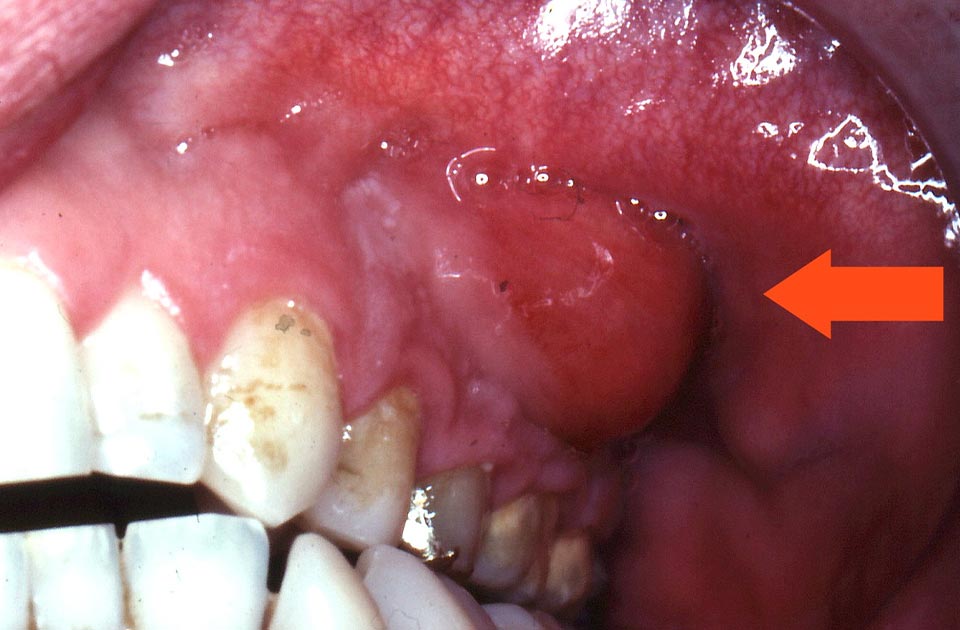

- تورم: تورم در لثه یا صورت در ناحیه دندان عفونی. این تورم ممکن است بهطور ناگهانی ظاهر شود و با افزایش عفونت، شدت آن بیشتر شود.